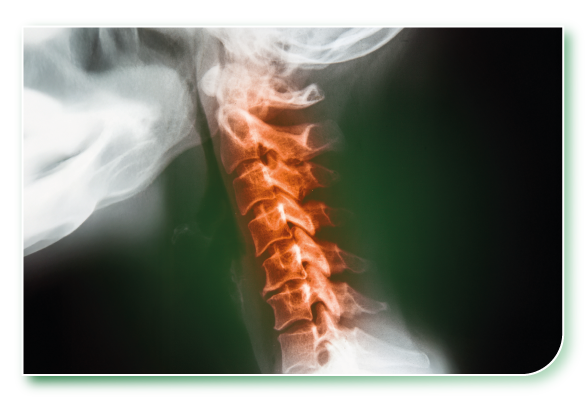

2. 頸椎退化/關節病變

年齡增長後,椎間盤、頸椎關節出現退化性改變,如骨刺、椎間盤突出,壓迫神經,引起放射痛。

1. 頸椎病變(Cervical Spondylosis)

頸椎退化形成骨刺或椎間盤突出,壓迫神經,引起頸痛、頭暈、手麻等問題。

2. 頸椎椎間盤突出(Cervical Disc Herniation)

壓迫脊神經或脊髓時會導致放射性疼痛或肌力下降,嚴重時影響日常活動能力。

5. 頸椎狹窄症(Cervical Spinal Stenosis)

脊髓管變窄導致神經壓迫,除了肩頸痛外,可能出現手腳麻痺或步態不穩。